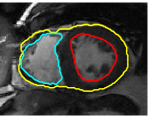

IV-A Tracking Multiple Regions

In cardiac image analysis, there are multiple structures (the right and left ventricles, and myocardium) that all useful and should be segmented. Our method is easily adaptable to this case. Indeed, computation of in Section III-C can be readily generalized. In general, multiple level sets should be used to represent multiple regions. However, in our case of interest (ventricles and surrounding epicardium), the regions form a rather simple topology (see Figure 3), and all regions can be represented using a single level set.